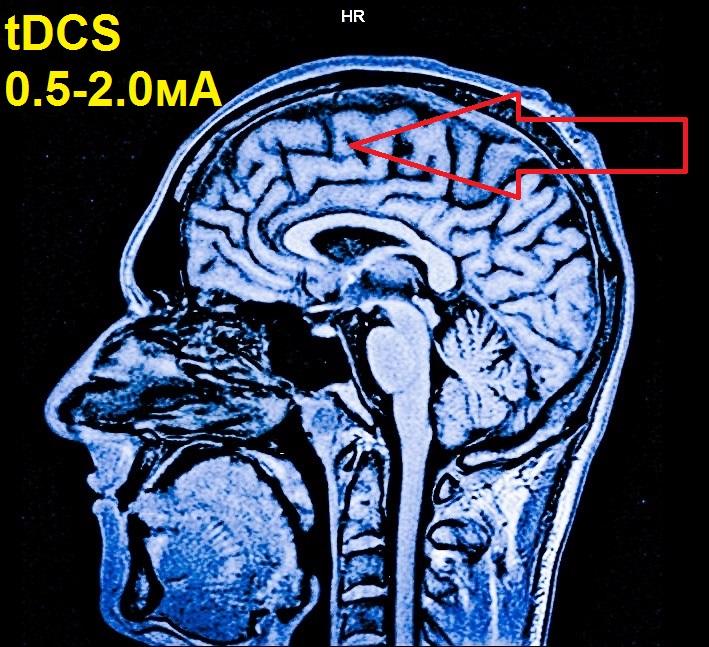

Всем привет! О преимуществах и эффективности технологии: tDCS – транскраниальной стимуляции мозга электричеством. Если коротко: это способ поляризовать «подзарядить» нейроны постоянным током малой силы. Написано миллион статей и научных работ в интернете. И что из этого всего чистая правда, а что просто фантастика. Лучший способ проверить и по-настоящему разобраться в этом — испытать эту технологию непосредственно на самом себе. Что я, как любитель странных гаджетов, будучи электронщиком натуралистом или просто воинствующим сангвиником и решил сделать.

Схема-то простая: два электрода с током от 0.5 до 2 мА… но цены будто он должен заряжать не только мозг, но и чьи-то кошельки.